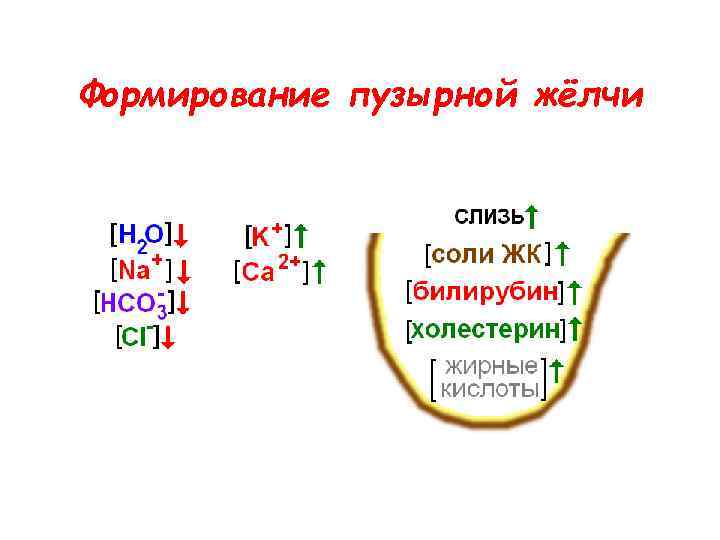

Формирование пузырной жёлчи

Формирование пузырной жёлчи

Формирование пузырной жёлчи

Формирование пузырной жёлчи

Состав печёночной и пузырной жёлчи

Состав печёночной и пузырной жёлчи